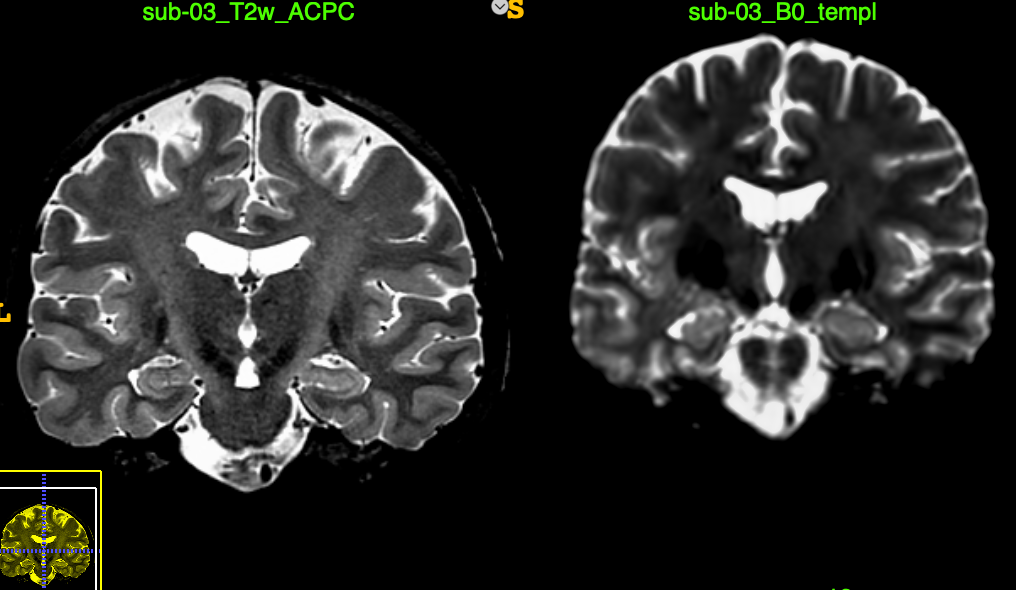

Hi, I am trying to use mrregister to align a B0 image to a T2w image. They both are of high quality, and in general aligning them works easy, and reliably no matter what option I choose when using ITKSnap or SPM.

mrregister sub-03_B0_templ.mif sub-03_T2w_ACPC.nii.gz -type affine_nonlinear -nl_warp W_s2t.mif W_t2s.mif -mask1 sub-03_templateMask.nii.gz -mask2 T2mask.nii.gz

The output is completely out of wack.

T2toDWI

And yes one of these images is a B0 from a dataset with 104 directions 32@1000 and 64@2500